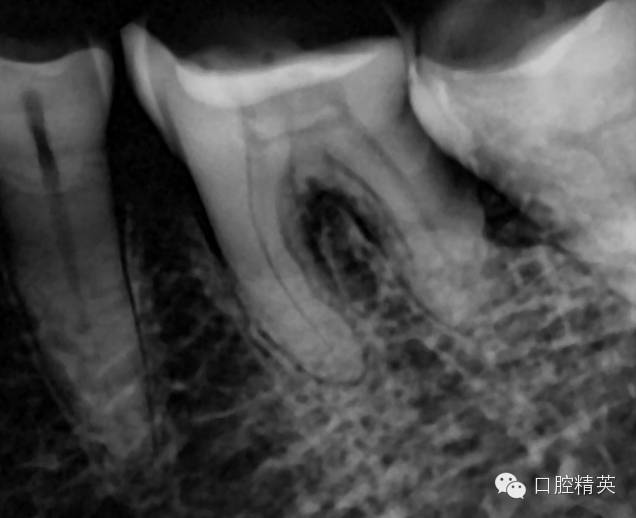

病例是36一次性根充,患者女性,68岁,半年前因冷热不适36外院有充填史,但无好转,近日加重,夜间痛自发痛,疼痛放散至头面部,查:36冷测(++)扣痛阳性,不松,牙髓电活力测试17,龈正常,诊断:不可逆性牙髓炎

这是个严重钙化的牙齿

严重钙化,打开根本找不到根管口![今天的病例,36一次性根充]()

超声去除钙化物,测量根管长度,逐级预备到9号先锋锉,并配合大量次氯酸钠和edta冲洗,冲洗后髓底非常干净清楚,特别利于你找到根管

由于近中舌根过于弯曲,所以采用tf镍钛锉预备到30#06锥度,edta,次氯酸钠超声荡洗后,干燥

iroot根充

iroot是生物陶瓷类材料,类似mta,我最喜欢它的固化膨胀效果,根尖封闭效果更好。